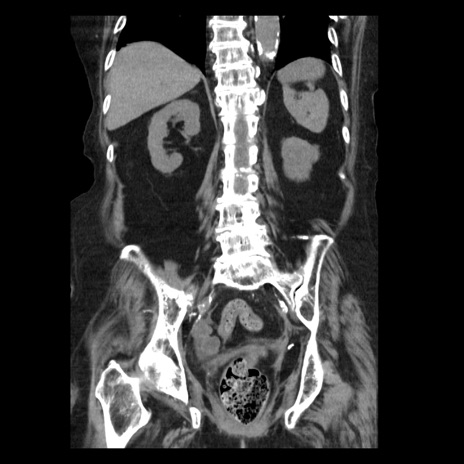

症例14(冠状断像)

【症例】 90歳代女性

【主訴】 腹痛・嘔吐

【現病歴】今朝から左側腹部痛を認めた。 経過観察していたが、嘔吐を認めたため来院。

【既往歴】 子宮癌術後

【身体所見】 意識清明、BP 127/54mmHg、P 98bpm Sp02 95%(RA)、BT 35.8°C、腹部平坦・軟腸ぜん動音聴取良好、右下腹部圧痛(+) 反跳痛なし

【データ】WBC 9800、CRP 0.46